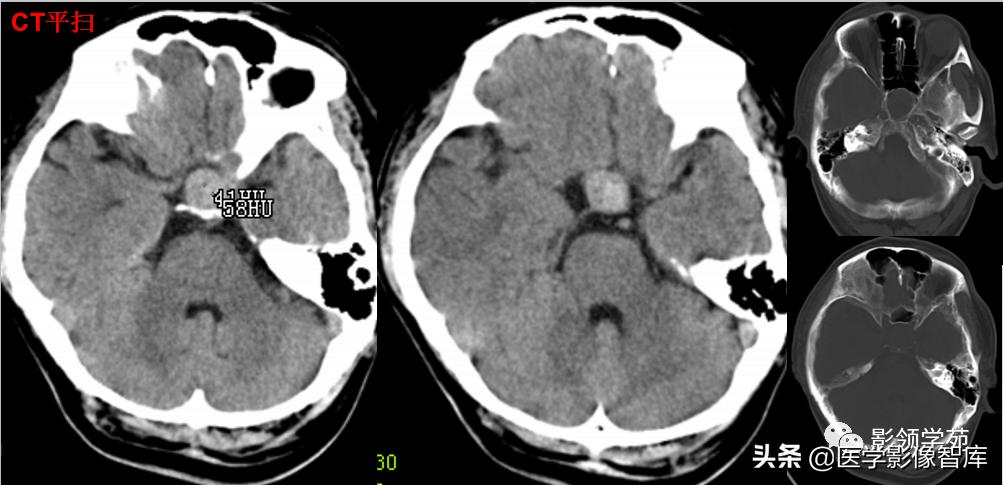

男 49岁, 肢端麻木2月。偶头晕头痛

鞍内及鞍上见一类圆形实性占位病变,边界尚清楚,密度欠均匀,CT值约41-58HU。垂体窝扩大,鞍背骨质稍变薄。

鞍区见一较大肿块,形态不规则,边界清楚,T1WI呈等信号,T2WI呈高低混杂信号;

矢状面和冠状面上可见典型束腰征、雪人征(腺瘤通过鞍膈向上生长时,由于受到鞍膈的限制而形成对称的切迹)。

病灶不均匀 明显强化。视交叉、垂体柄受压上移。